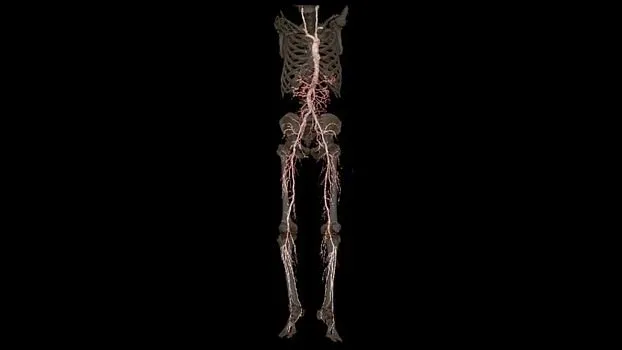

Клинические изображения

Клиническая эффективность

В КТ-исследованиях больше всего времени уходит не на само сканирование, а на подготовку пациента, реконструкцию изображений и создание заключительного отчета. С Revolution Ascend вы можете легко размещать пациентов с высоким ИМТ на столе и эффективно проводить интервенционные процедуры и любые другие исследования нажатием всего лишь двух кнопок.